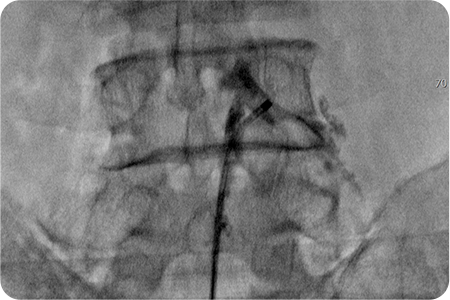

풍선확장술

풍선이 내장된 특수 카테터를 척추에 삽입하여

좁아진 척추관의 폭을 넓히는 치료법입니다.

신경에 직접 유착방지제와 항염증제를 주입해 통증을 줄이고,

풍선을 부풀려 신경 주변 공간을 넓혀 척추관 협착증에 효과적입니다.

풍선확장술은 꼬리뼈를 통해 특수 카테터를 삽입해 풍선을 부풀려 신경 주변 공간을 직접 넓히는 최신 비수술적 시술입니다.

풍선으로 눌린 조직을 밀어내어 신경 압박을 완화하고, 약물을 정확히 병변 부위에 전달해 통증을 줄이는 장점이 있습니다.

풍선확장술 치료과정